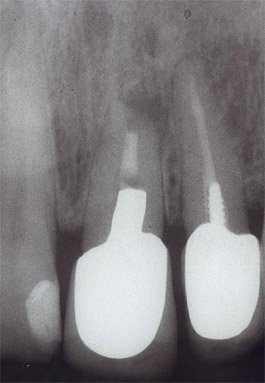

• Röntgenbilder

• Übersichtsröntgenbild

• Zustand von bereits angefertigten Zahnrekonstruktionen (Füllungen, Kronen, usw.)